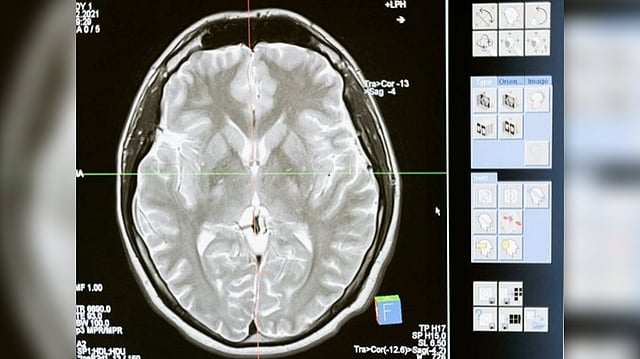

WASHINGTON: Scientists at the UNC School of Medicine have mapped the surface of the cortex of the young human brain with unprecedented resolution, revealing the development of key functional regions from two months before birth to two years after.

The cortex thickens markedly during this interval, and grows at an even faster pace in terms of surface area, by forming complicated cortical folds. Disruptions to cortical thickening and expansion in this phase have been linked to autism and schizophrenia. However, neuroscientists haven't had as detailed an understanding of this developmental phase as they would like. In particular, they've had a need for more comprehensive, high-resolution mapping, across the fetal-to-toddler age range, that divides or "parcellates" the developing cortex into distinct regions with their own growth rates -- especially surface area growth rates. In the study, Li and colleagues performed just such a mapping. They first gathered a set of 1,037 high-quality magnetic resonance imaging (MRI) scans of infants in the third-trimester-to-two-year age interval.

The scans came from two other research projects, the UNC/UMN Baby Connectome Project (BCP) and the Developing Human Connectome Project. The team analyzed the scan data using state-of-the-art, computer-based image-processing methods, essentially dividing the cortical surface into a virtual mesh containing thousands of tiny circular areas, and calculating the surface expansion rate for each of these areas.